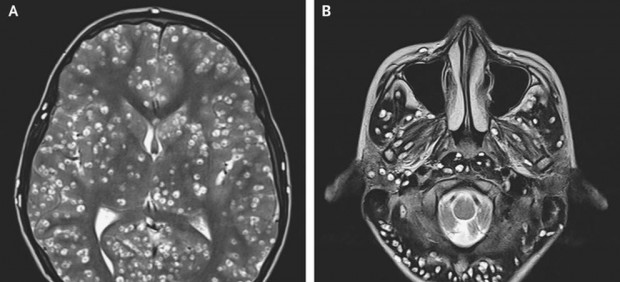

Según un informe publicado en el New England Journal of Medicine, los médicos, después de examinarlo, ordenaron una resonancia magnética y exámenes de ultrasonido. "La resonancia magnética mostró numerosas lesiones quísticas bien definidas en toda la corteza cerebral y el tronco encefálico y el cerebelo que eran compatibles con la neurocisticercosis", señalan los médicos doctores Nishanth Dev y S. Zafar Abbas, del Colegio Médico y Hospital ESIC en Faridabad.

La Organización Mundial de Salud (OMS) define la neurocisticercosis como una enfermedad parasitaria del cerebro "causada por la tenia porcina" (Taenia solium). "El ser humano se infecta al comer carne mal cocinada, sobre todo de cerdo, al beber agua contaminada por huevos de tenia o por malas prácticas higiénicas", señala la OMS.